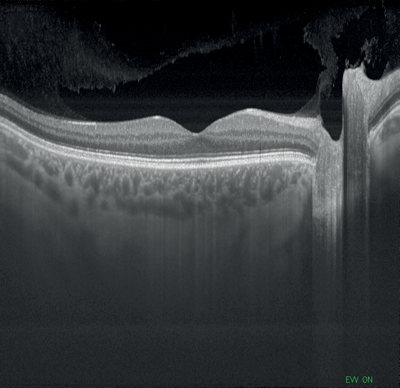

Figures 1-4: Swept-source OCT (DRI OCT-1 Triton, Topcon) images of healthy eyes that clearly delineate features in the vitreous, including area of Martegiani, bursa premacularis and posterior hyaloid, right through to the sclera, in the same single scan.

Topcon’s newly-introduced swept-source DRI OCT Triton can capture 256 B-scans in less than three seconds, with high speed scanning of 100,000 A-scans per second and a 1050nm wavelength which can penetrate easily through cataracts and haemorrhages. It features widefield 12 by 9mm scan screens for both glaucoma and macular pathology in one scan, with consistent signal strength from cortical vitreous to the sclera with an average of up to 128 times, automatic detection of seven retinal layers, as well as 2.6 micron digital resolution. The DRI OCT Triton has a built-in high resolution colour fundus camera, fundus guided acquisition (SmarTrack) and the option of an anterior imaging module. The Triton Plus also features fundus autofluorescence and fluorescein angiography, and an OCT angiography module is currently under development.